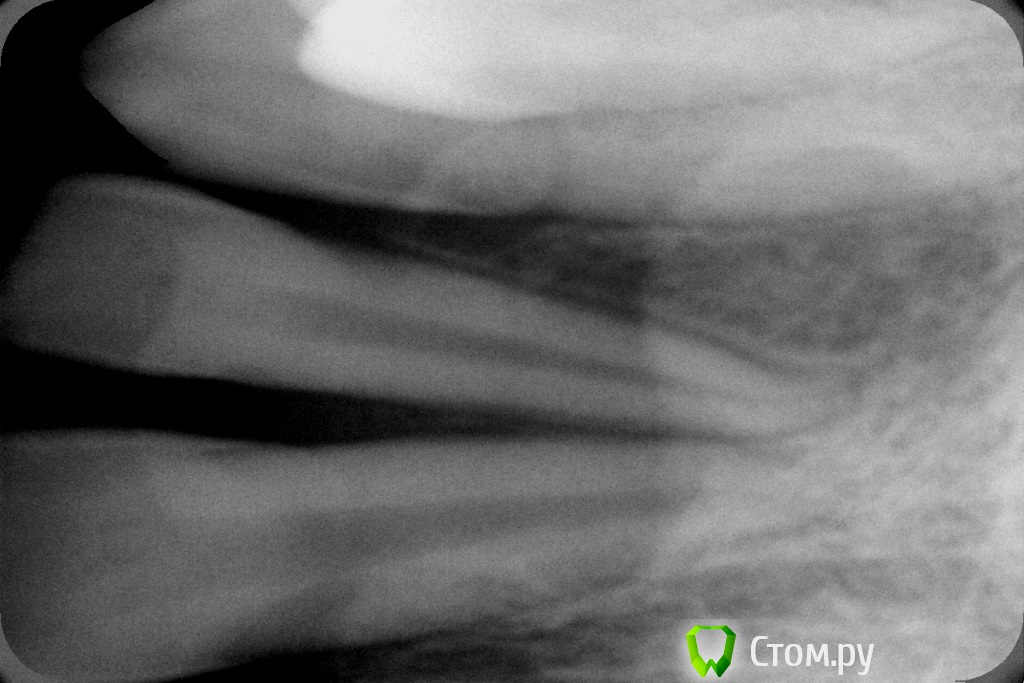

johniola Опубликовано 7 мая, 2014 Поделиться Опубликовано 7 мая, 2014 (изменено) Мальчик 13 лет.Эпулис? Какое мнение у коллег?Простите за фото. Изменено 7 мая, 2014 пользователем johniola Ссылка на комментарий

red_butler Опубликовано 7 мая, 2014 Поделиться Опубликовано 7 мая, 2014 снимок, удалять и на гистологию Ссылка на комментарий

Maxfac Опубликовано 7 мая, 2014 Поделиться Опубликовано 7 мая, 2014 биопсия в первую очередь, затем операция!+1Иногда за похожими штуками скрывается ОБК Ссылка на комментарий

mr.Fog Опубликовано 9 мая, 2014 Поделиться Опубликовано 9 мая, 2014 А образование на ножке, на узкой или широкой? Какое время существует, не чрезвучайно ли использует флос? Соматически здоров? Инцизионная хирургическая биопсия в помощь- в данном случае иссечение с вестибулярной стороны с захватом здоровой слизистой. Тампоном с 3%h2o прижатья, если нет коагулятора. Ссылка на комментарий

johniola Опубликовано 16 мая, 2014 Автор Поделиться Опубликовано 16 мая, 2014 Чем закончилось?Да закончилось, это фиброзный эпулид,уже почикали Ссылка на комментарий